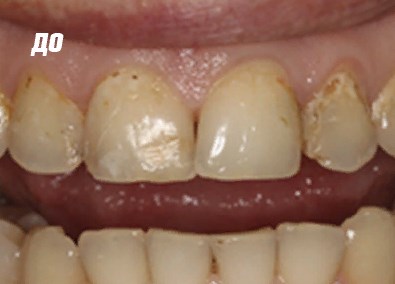

Фото ДО

Фото ПОСЛЕ

Наведите для просмотра

Реставрация фронтальной группы зубов